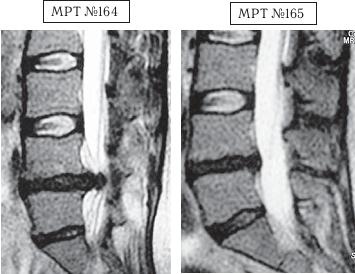

На МРТ № 164 наблюдается поясничный отдел позвоночника: секвестрированная грыжа межпозвонкового диска в сегменте LIV-LV с разрывом задней продольной связки, абсолютный стеноз спинномозгового канала.

На МРТ № 165 состояние поясничного отдела позвоночника после лечения методом вертеброревитологии: отсутствие грыжи межпозвонкового диска в сегменте LIV-LV, отсутствие стеноза спинномозгового канала, восстановление физиологического лордоза.

Обратите внимание на форму позвоночника и расположение позвонков в данном отделе до лечения (МРТ № 164). Вы увидите явное сглаживание поясничного лордоза, клиновидную форму межпозвонкового диска LIV-LV с расширением кзади (где и образовалась секвестрированная грыжа межпозвонкового диска). Как вы помните, наш позвоночник устроен так, что при его растяжении (вытяжении, висе на турнике и так далее) вначале растягиваются суставы, потом задние отделы межпозвонкового диска, а передние его отделы сближаются. Таким образом, содержимое межпозвонкового диска под давлением устремляется от передних отделов к задним. Напомню, что именно задние отделы фиброзного кольца наиболее слабые и легко уязвимые, поэтому именно в них и образуются протрузия или грыжа межпозвонкового диска. Таким образом, при вытяжении позвоночника получается перерастяжение задних отделов фиброзного кольца, что при наличии грыжи межпозвонкового диска способствует ускорению процесса разрыва фиброзного кольца и увеличению размеров грыжи, вплоть до осложнения секвестром. Эти процессы и наблюдаются на МРТ № 164.